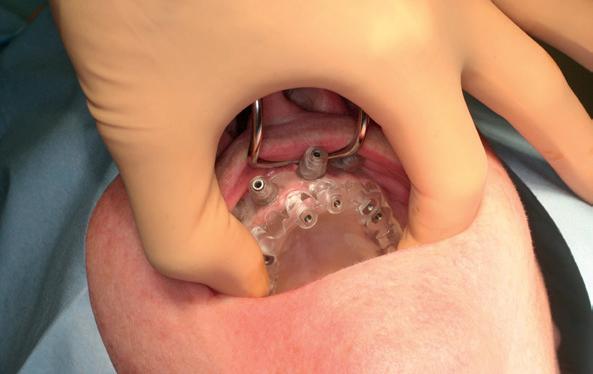

Zitting 4 plaatsen PMMA brug & multi-unit abutments

Wanneer de tijdelijke brug retour komt, dienen eerst de healing abutments verwijderd te worden en de implantaten uitgespoeld te worden met Blue M spoelmiddel in een monoject. De brug paste niet direct op de interne verbindingen van de implantaten, omdat deze daarvoor niet parallel genoeg stonden, omdat de kaak in een curve liep. Daarom wordt over het algemeen gekozen voor multi-unit abutments die op de implantaten worden gedraaid. Hierdoor wordt de brug op coronaal hoger niveau geplaatst en door de multi-unit abutments wordt een open inzetrichting verkregen.

De PMMA tijdelijke brug werd direct op de multi-unit abutments geschroefd met kleine schroefjes. De schroefgaten van de brug werden afgesloten met teflontape en composiet. Indien nodig, kon er aan de PMMA brug de occlusie en articulatie geslepen worden. In deze casus was dat verder niet nodig. De

12. Na plaatsen van multi-unit abutments

13. Na plaatsen tijdelijke brug op de implantaten